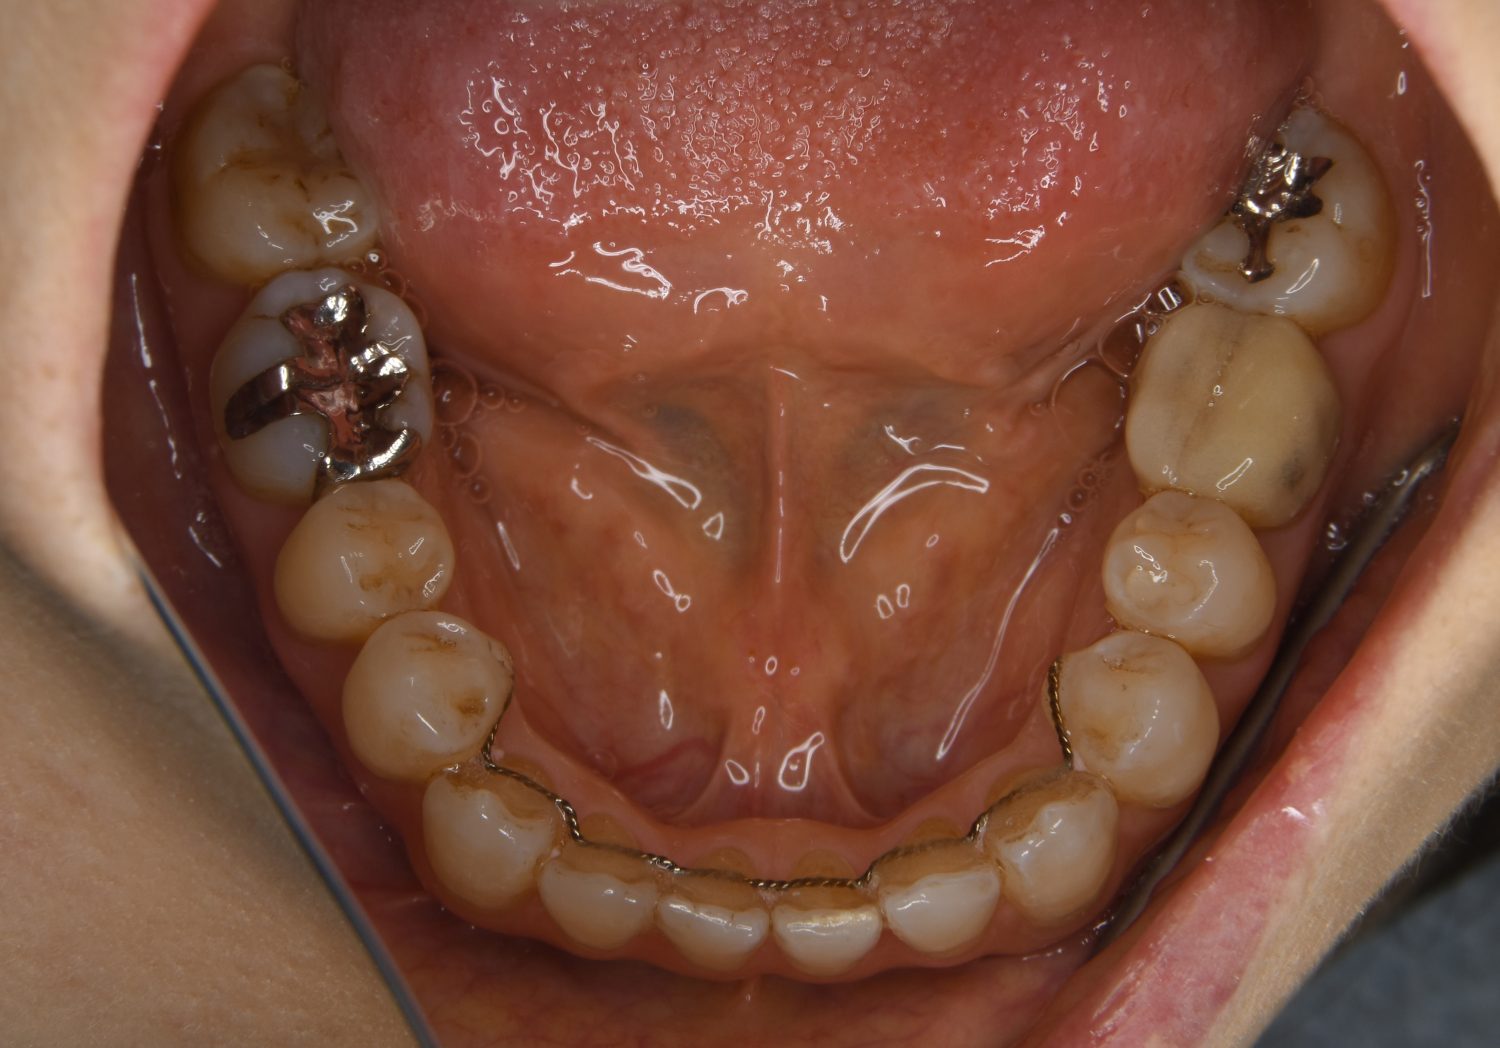

叢生の症例紹介②

Before

主訴

歯の凸凹を治したい。

治療内容

アライナー(インビザライン)にて非抜歯で治療を行いました。

治療費

1,150,000 円(税込)

治療期間

26ヶ月

通院回数

14回

想定されたリスク

※歯根吸収、歯肉退縮、歯髄壊死、顎関節症状

※アライナー(インビザライン)は日本の薬機法未承認の矯正装置であり、医薬品副作用被害救済制度の対象外となる場合があります。

上下前歯部に叢生(凸凹)が認められる状態でした。歯列の遠心移動を行うことで機能面および審美面が改善されました。